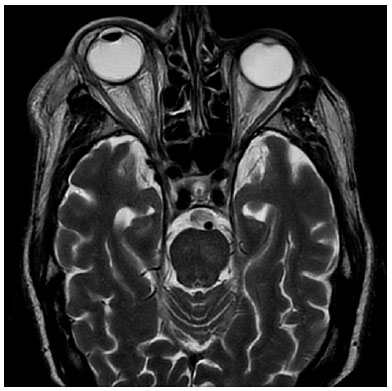

In the ophthalmologic exploration, an amaurotic eye with areflexic myosis, conjunctival hyperemia, and intraocular pressure (IOP) of 46 mmHg was observed, without other significative changes. The patient was treated with intravenous (IV) 20% mannitol at 250 ml once and acetazolamide 250 mg orally every 8 hours with subsequent IOP lowering. A few hours later, a remarkable proptosis is observed, accompanied by chemosis, vascular ingurgitation, and “frozen eye”. Under the suspicion of a retro-bulbar hematoma or carotid-cavernous fistula, emergency magnetic resonance imaging (MRI) and angio-MRI were performed. No signs of vascular disorders were discovered, except for an increase in soft tissue both in the pre- and post-septal spaces, without paranasal sinus occupation, compatible with orbital cellulitis (Figure 1). In the blood count, neutrophilia and leukocytosis were present.